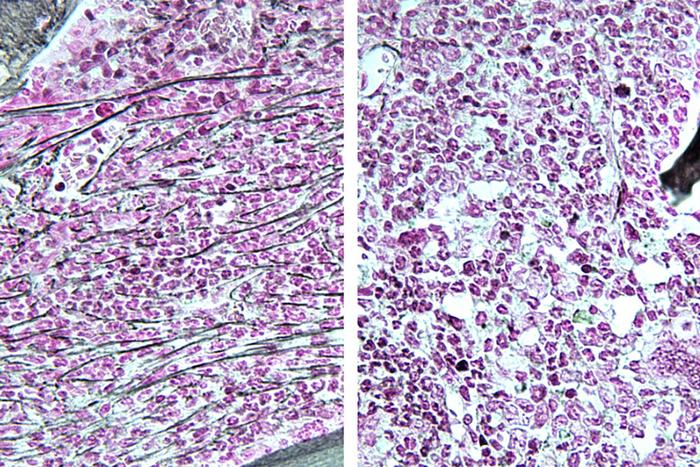

The studies offer a compelling narrative around RSK1 as a novel target. When RSK1 was inhibited in experimental models, evidence pointed to a reversal of disease characteristics, demonstrating the mechanism of action through which the drug may exert its effects. Mice treated with PMD-026 exhibited decreased fibrosis in their bone marrow, resembling that of healthy tissue, contrasting sharply with untreated counterparts who demonstrated severe disease manifestations.

Image Credits: TIM KONG AND ANGELO B. A. LARANJEIRA